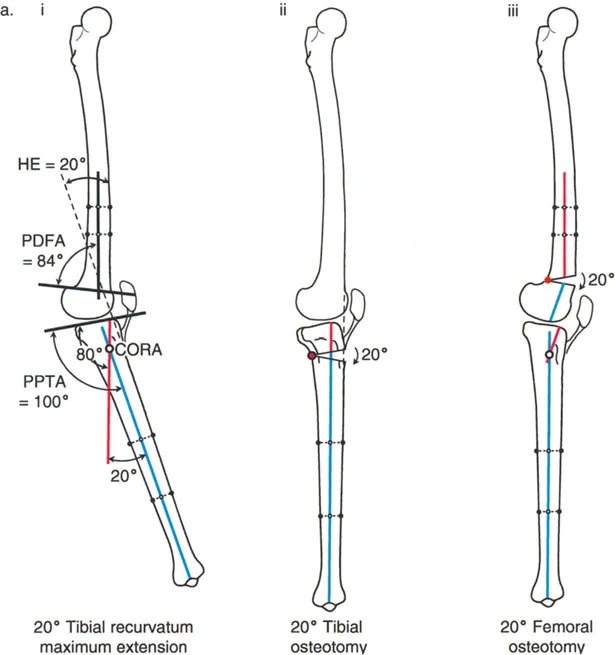

- زاوية الانحناء البعيدة للفخذ (PDFA - Posterior Distal Femoral Angle): تقيس زاوية الجزء السفلي من عظم الفخذ. القيمة الطبيعية حوالي 84 درجة. الزيادة في هذه الزاوية (أكثر من 84 درجة) تشير إلى ارتداد فخذي.

- زاوية الانحناء القريبة للظنبوب (PPTA - Proximal Posterior Tibial Angle): تقيس زاوية الجزء العلوي من عظم الساق. القيمة الطبيعية حوالي 80 درجة. الزيادة في هذه الزاوية (أكثر من 80 درجة) تشير إلى ارتداد ظنبوبي.

- مركز دوران الزاوية (CORA - Center of Rotation of Angulation): يتم تحديد هذا النقطة على الأشعة السينية لتحديد مكان التشوه العظمي بدقة، وهو أمر بالغ الأهمية لتخطيط عملية قطع العظم.

- الركبة الارتدادية بسبب الارتداد الفخذي:

- إذا كانت درجة فرط التمدد (HE) تساوي درجة الارتداد الفخذي (PDFA > 84°)، فهذا يعني أن التشوه كله ناتج عن عظم الفخذ.

- في هذه الحالة، يكون مركز CORA في الجزء البعيد من عظم الفخذ.

- الركبة الارتدادية بسبب الارتداد الظنبوبي:

- إذا كانت درجة فرط التمدد (HE) تساوي درجة الارتداد الظنبوبي (PPTA > 80°)، فهذا يعني أن التشوه كله ناتج عن عظم الساق.

- في هذه الحالة، يكون مركز CORA في الجزء القريب من عظم الساق.

أ. قطع العظم الفخذي لتصحيح الارتداد الفخذي:

- متى يتم إجراؤها: عندما يكون التشوه الرئيسي في عظم الفخذ البعيد.

- الإجراء: يتم إجراء قطع للعظم (عادة قطع عظم انثناء) في الجزء البعيد من عظم الفخذ، عند مركز دوران الزاوية (CORA)، لإعادة محاذاة العظم.

- الهدف: تصحيح فرط تمدد الركبة واستعادة المحاذاة الطبيعية.

- مثال: لتصحيح ارتداد فخذي بمقدار 20 درجة، يتم إجراء قطع عظم انثناء فخذي بمقدار 20 درجة.